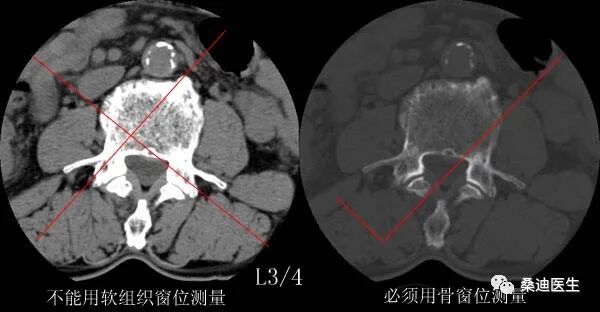

侧隐窝的测量必须满足两个条件:一是必须用骨窗位来测量,二是测量层面必须是完整的椎体层面,即显示出椎弓根的层面。

侧隐窝的测量方法是关节突的内侧缘与椎体后部的连线的长度:

侧隐窝宽窄的判断,小于3mm为肯定狭窄,3mm-5mm为可疑狭窄,大于5mm则不狭窄。